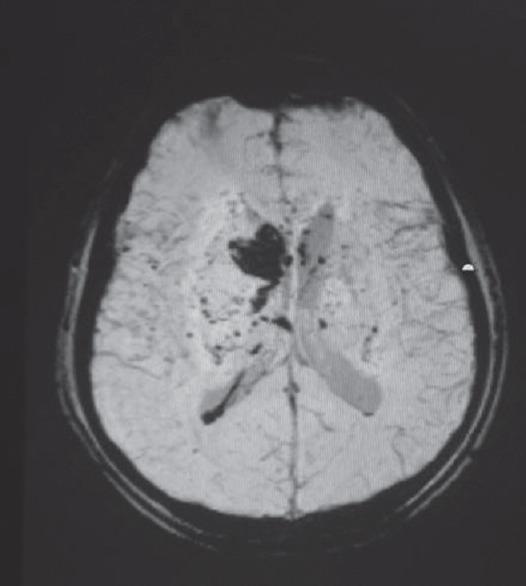

快速进展性认知衰退综合征——我们的经验

Syndromes of Rapidly Progressive Cognitive Decline-Our Experience.

RESULTS AND CONCLUSIONS

Out of 144 patients 42 had immune-mediated encephalopathy, 18 had Creutzfeldt-Jakob disease, 3 had Vitamin B12 deficiency, 63 had infection with neurocysticercosis, 7 had tuberculosis, 2 had HIV, 1 had herpes simplex encephalitis, 1 had neurosyphilis, 1 Whipples disease, 1 had Subacute Sclerosing Panencephalitis, 1 had Mass lesion, 3 had Frontotemporal dementia, and 3 had small vessel disease. Good majority of these patients have infective and immune-mediated causes and less number belong to degenerative group. Therefore, caution is needed to look for treatable cause as it carries a different treatment options and outcome.

结果与结论

144例患者中,42例患有免疫介导性脑病,18例患有克雅氏病,3例患有维生素B12缺乏症,63例患有神经囊尾蚴病感染,7例患有结核病,2例患有艾滋病,1例患有单纯疱疹性脑炎,1例患有神经梅毒,1例患有惠普尔病,1例患有亚急性硬化性全脑炎,1例患有占位性病变,3例患有额颞叶痴呆,3例患有小血管疾病。这些患者中绝大多数有感染性和免疫介导性病因,属于退行性病变组的较少。因此,需要谨慎寻找可治疗的病因,因为其治疗选择和结果不同。